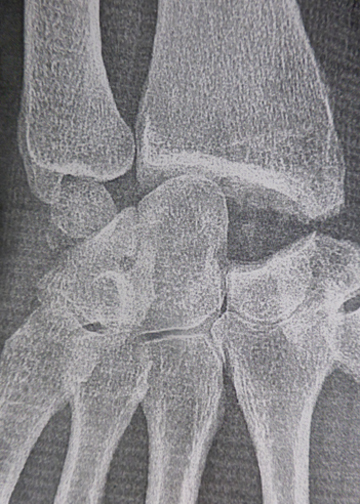

Rupture complète du ligament scapholunaire avec écartement des deux os appelé diastasis scapholunaire.